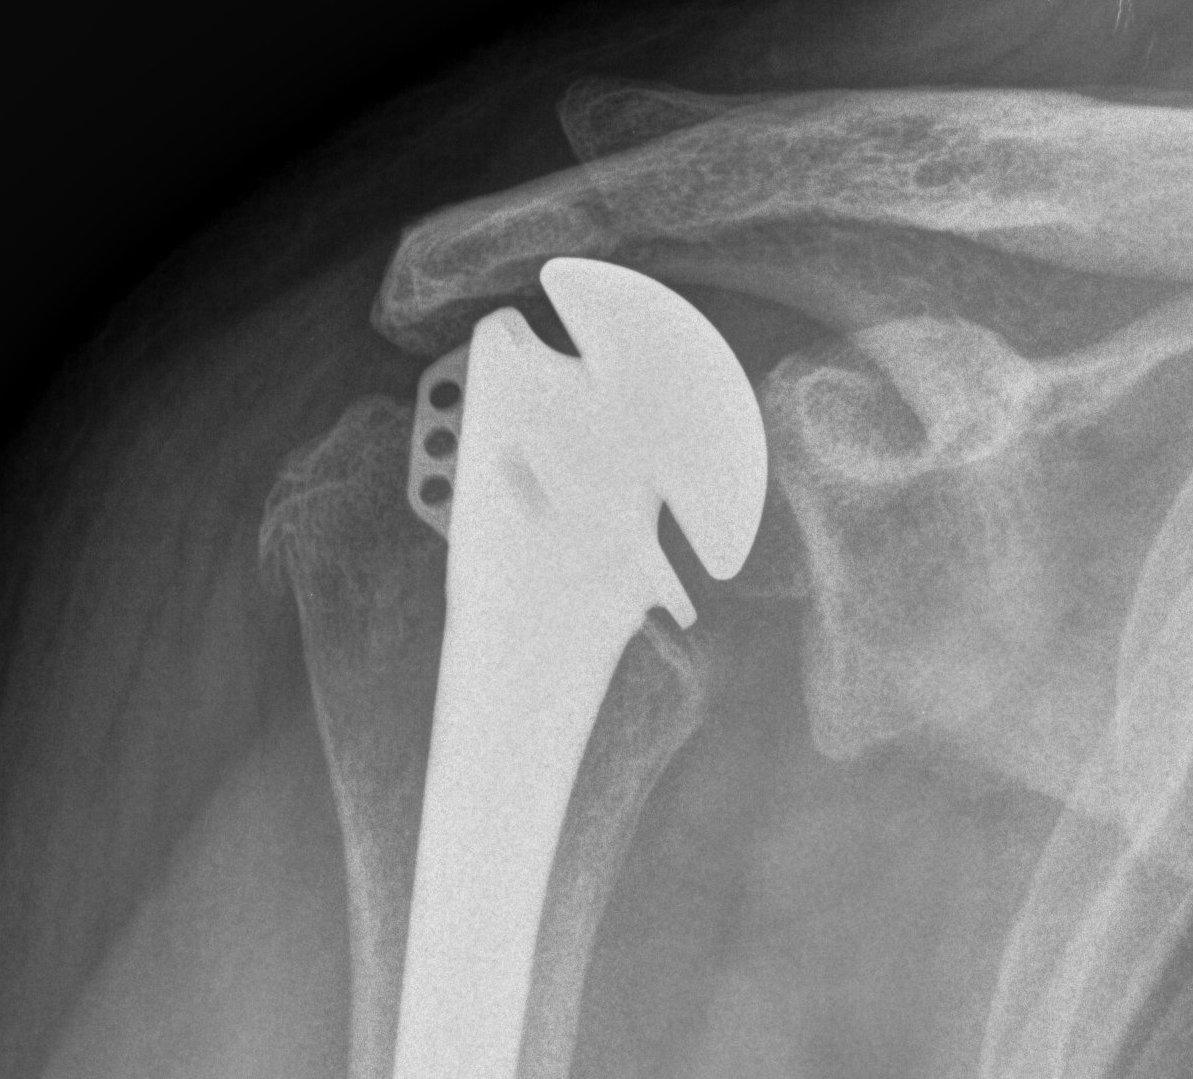

TSR Anterior Instability LateralTSR Anterior Instability AP

TSR Posterior DislocationRevision for Posterior Dislocation TSR Combined Anterior Posterior Approach